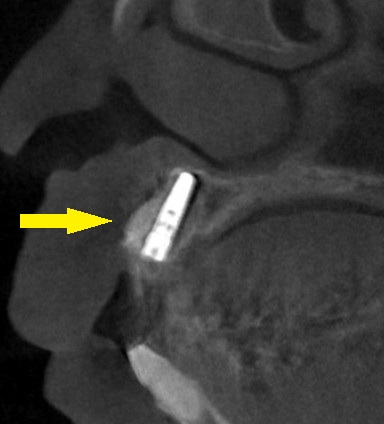

下の写真3段目が手術後のCTとなります。